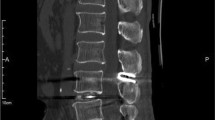

At the last follow-up, VAS and ODI scores decreased significantly in the two groups compared with preoperative values (P < 0.05). VAS and ODI scores were not statistically significant in the two groups at preoperation and final follow-up (P > 0.05). One patient in the OLIF group developed ASD at the final follow-up, and the incidence of ASD was 2.78% (Table 2); this patient chose conservative treatment. Two patients in the TLIF group developed ASDis, and the incidence of ASDis was 5.56%. One patient chose conservative treatment, and the other patient chose TLIF revision surgery (Fig. 1).

A, B Lateral X-ray and sagittal magnetic resonance image of lumbar in a 48-year-old female patient complaining of lumbar pain with right lower extremity pain. It showed L4 degenerative lumbar spondylolisthesis and L4-5 disc degeneration. C, D 47 months after TLIF, this patient again complained of low back pain with numbness in both lower extremities. Lateral X-ray and sagittal magnetic resonance image of lumbar showed L3 spondylolisthesis and L3-4, L5-S1 intervertebral disc degeneration aggravated relative to preoperative. E The patient selected TLIF revision surgery. Lateral X-ray of lumbar spine showed satisfactory L3 reduction